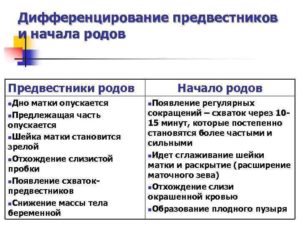

Даже повторнородящие женщины часто пропускают предвестники начинающихся родов, хотя, казалось бы, должны помнить, как начинается процесс появления малыша. Итак, на что следует обратить внимание:

- На последних неделях женщина может ощущать тренировочные (ложные) схватки. Когда схватки становятся более ощутимыми, болезненными и продолжаются с регулярным интервалом, пора ехать в роддом. Выпейте таблетку но-шпы, постойте под теплым душем, полежите или посидите в расслабленном состоянии. Если болевые ощущения исчезли, вызывать бригаду скорой помощи рано.

Непосредственно перед родами в организме женщины происходит множество изменений: изменяется состояние связок, мышц, меняется гормональный фон, происходят психологические процессы, которые не могут оставаться незаметными. Это и есть предвестники приближающихся родов.

На 39 неделе беременности предвестники родов у первородящих несколько отличаются от симптомов, которые могут наблюдаться у женщин, вынашивающих второго ребенка. Специалисты выделяют такие основные предвестники родов на 39 неделе беременности, которые могут проявляться за неделю до начала родовой деятельности:

Предвестники родов у повторнородящих отличаются своей скоротечностью. То есть, после появления определенных симптомов, роды могут начаться практически сразу. Быстротечные роды могут представлять угрозу для ребенка. Поэтому, когда тридцать девятый недельный период беременности у повторнородящих женщин связан с тем, что болит живот и тянет поясницу, то лучше сразу обратится в роддом.

Предвестники родов у повторнородящих и первородящих женщин всегда сопровождаются учащением ложных схваток. При этом сильно болит поясница и тянет живот. Если такие симптомы появились, то нужно ожидать начало родов в ближайшее время, а это значит, что необходимо срочно отправляться в роддом.

Ярким предвестником надвигающихся родов является отхождение околоплодных вод. Если в одночасье появилось много прозрачных выделений, то произошедший факт указывает на то, что нужно не дожидаясь схваток отправляться в роддом. С другой стороны, иногда бывает так, что схватки усиливаются, но воды не отходят. В этом случае в процессе родов может понадобиться прокалывание плодного пузыря.

В течение 39 недели беременности могут участиться схватки, причем на этом этапе схватки могут быть двух типов: «ложные» и «родовые».

Ложные схватки могут начаться за несколько недель , или даже месяцев до ожидаемого срока родов. Такие схватки помогают ребенку принять правильное положение в утробе матери, а также подготовить матку к родам.

Такие схватки нерегулярны, непродолжительны, ощущаются преимущественно в нижней и передней частях живота.

Родовые же схватки регулярны, ритмичны, не ослабевают, учащаются с нарастающей силой. Обычно они имеют место после отхождения околоплодных вод. При этом раскрытие шейки матки происходит на 4 см. Начавшимися роды формально считаются только после появления сильных и частых схваток.

Боль при схватках приступообразная, четко ощущается её возникновение, усиление, достижение пика и постепенное уменьшение, потом наступает период без болевых ощущений. Сначала схватки перед родами идут с промежутком 15-30 минут и длятся 10-15 секунд.

Первые несколько часов они приносят скорее небольшой дискомфорт, чем боль. Постепенно продолжительность и сила схваток увеличиваются, а интервалы уменьшаются.

Как происходят схватки? Схватки перед родами развиваются постепенно, поэтому можно выделить три стадии:

- Первая стадия — начальная, длится 7-8 часов. В это время схватки происходят с интервалом примерно в 5 минут, а продолжительность их — 30-45 секунд.

- Вторая фаза — активная. Ее продолжительность около 5 часов, сокращения матки становятся чаще и длятся дольше — с интервалом 2-4 минуты, продолжительность схваток достигает 60 секунд.

- Последняя, переходная, фаза — длиной от получаса до 1,5 часов. Схватки становятся еще чаще и дольше. Они могут происходить с промежутком в минуту и иметь продолжительность от 70 до 90 секунд.

Ряд симптомов, появляющихся у большинства беременных за несколько дней до родов, называют предвестниками. Их роль – обозначить готовность организма к серьезному процессу. Женский организм активно готовится к родам для того, чтобы ребенку и роженице было проще преодолеть все трудности рождения.

- Самый яркий предвестник родов – это тренировочные схватки. Матка пробует себя, готовится к родовой деятельности. Предвестниковые сокращения аритмичны. Могут длиться несколько недель и, как и сокращения Брекстона-Хикса, призваны подготавливать матку к работе во время родов. Подобные тренировки помогают созреванию шейки матки, расширяя и укорачивая ее. До 37 недели схватки не являются предвестниковыми. Не путайте тренировочные схватки с тонусом матки и настоящими родовыми схватками. Различия существенны, хотя возникают все эти сократительные активности по одному принципу: мышцы матки напрягаются, становясь плотными, четко очерчивают ее контур, возникает тяжесть в области крестца и внизу живота. Предвестниковые схватки короткие и относительно безболезненные. Наблюдаются до 6 раз в сутки, способствуют активизации кровообращения и обеспечивают ребенку доставку большего объема питательных веществ. Тренировочные сокращения проходят сами или смягчаются при приеме дротаверина или постановке расслабляющей свечки, при массаже, принятии душа. Тонус матки – это длительное, болезненное, не проходящее напряжение, угрожающее плоду. Родовые схватки, в отличие от тренировочных, регулярны, их интенсивность и частота нарастают. От них невозможно отвлечься.

Появление предвестников вовсе не означает, что наступили роды. Иногда предвестники могут длиться 2-3 недели. Длина беременности зависит от характера менструального цикла женщины. Вероятность рождения малыша на 39 неделе наиболее велика у женщин, с промежутком между менструациями в 21 день.

Классическое начало родов для первородящих – это не сочетание предвестников, а только регулярные схватки, нарастающие со временем. При нормальной беременности ехать в роддом нужно при 10-минутном перерыве между маточными сокращениями.

Рожавшим женщинам поездку в роддом нужно планировать чуть раньше. В силу анатомических особенностей шейка их матки обладает более широким просветом, а также сильнее отзывается на гормональную стимуляцию.

Предвестники у повторнородящих выражены сильнее и замечают их раньше. К примеру, больше жидких выделений, объемнее пробка, повторнорожающих женщин сильнее беспокоят пробные сокращения.

Отмечается также, что роды могут быть быстрее, чем в первый раз, а предвестники наступают всего за сутки-двое до родоразрешения.